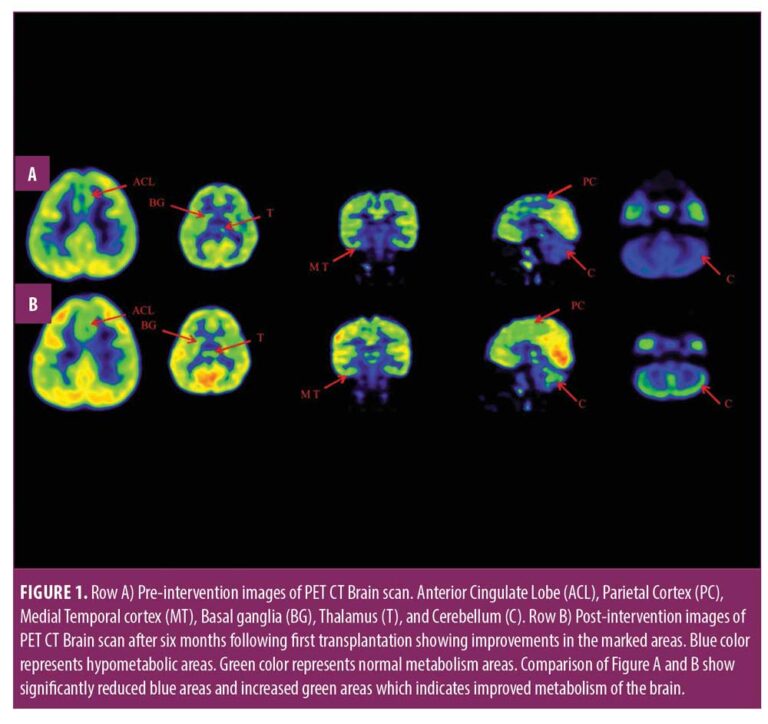

本報告中,我們治療了一名患有痙攣性雙癱性腦癱的兒童,在對康復反應有限后,采用了多種細胞療法。臨床改善的結(jié)果與客觀量表相關(guān),例如粗大運動功能測量 (GMFM)、粗大運動功能分類系統(tǒng) (GMFCS) 以及功能獨立測量 (FIM) 和 (PET CT) 腦成像研究。

在認知上,由于他定期上學,他的注意力持續(xù)時間和坐姿耐受力也得到了改善。GMFM分數(shù)從60.67提高到67。GMFCS等級由3級提升至2級;FIM評分從97分提高到99分。比較第一次細胞治療之前和之后7個月期間進行的腦部PET CT掃描結(jié)果,發(fā)現(xiàn)前扣帶回葉、頂葉皮層、內(nèi)側(cè)顳葉皮層、丘腦、基底神經(jīng)節(jié)和小腦(表1)。

在此,我們通過客觀量表(如FIM、GMFM和GMFCS)和正電子發(fā)射計算機斷層掃描腦神經(jīng)影像對比研究來監(jiān)測細胞療法后的療效。在16個月的治療過程中,GMFM評分從60.67分提高到81.88分,其中坐的領(lǐng)域從59分提高到60分,爬行和跪的領(lǐng)域從32分提高到40分,站的領(lǐng)域從6分提高到27分,走、跑和跳的領(lǐng)域從8分提高到32分。GMFCS 分級從第3級提高到第2級,因為孩子能夠騰出雙手坐在椅子上,能夠在沒有幫助的情況下在平整的地面上行走和奔跑,還能夠扶著欄桿爬樓梯。FIM分數(shù)從91分提高到99分,這表明他的功能狀況有所改善。

這項研究表明,多種干細胞療法結(jié)合神經(jīng)康復可有效改善腦癱患者的粗大運動功能和功能獨立性。自體BMMNC多次移植后進行強烈的神經(jīng)康復可加快神經(jīng)再生過程,這反過來又反映了患者殘疾程度和生活質(zhì)量的積極結(jié)果。PET CT掃描可以有效地用于監(jiān)測干預后細胞水平發(fā)生的變化。因此,多細胞療法是安全、可行的,并且可以有效地與腦癱的神經(jīng)康復相結(jié)合作為增強治療。